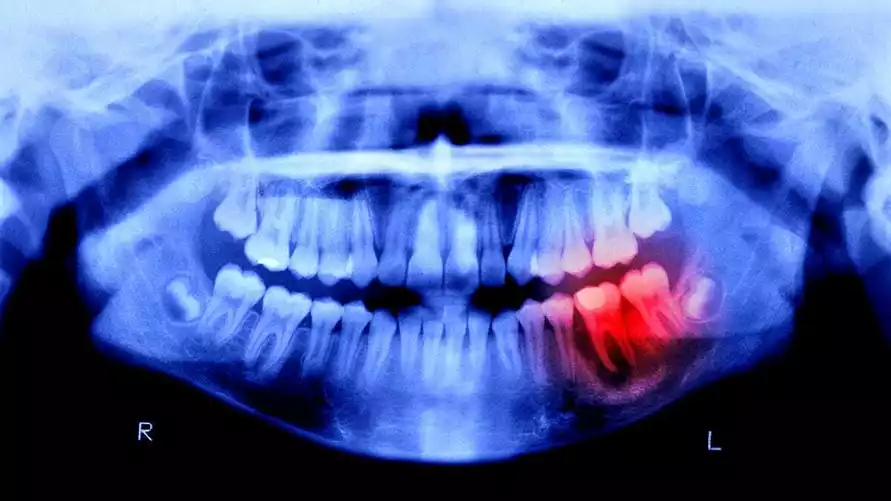

Наши кости умеют срастаться после переломов. А вот зубы — нет. Если постоянный зуб потерян, на его месте уже ничего не вырастет. Именно поэтому импланты и протезы стали золотым стандартом в стоматологии с древнейших времен. Но у них есть недостатки: они могут отторгаться, не имеют естественной «амортизации» и не чувствуют давления, как настоящие зубы.